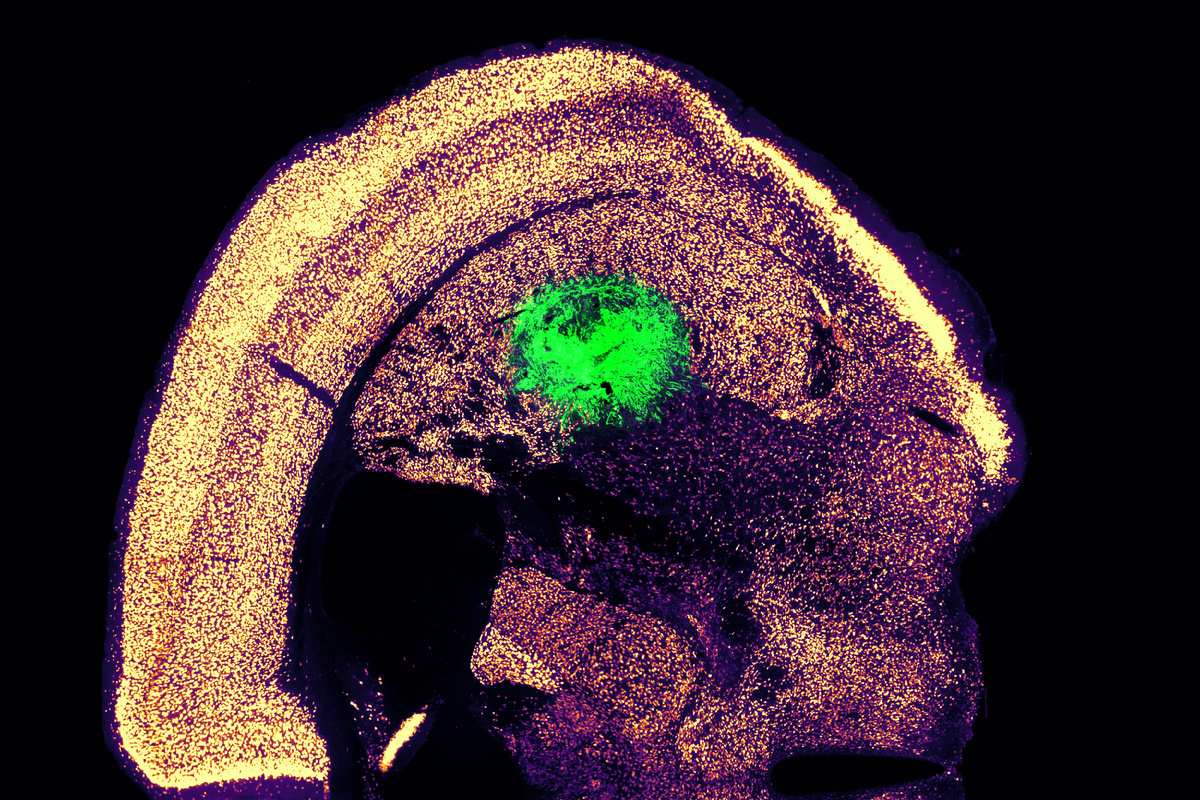

Чтобы проверить функциональность созданных в лаборатории нейронов, команда MIT в сотрудничестве с исследователями из Бостонского университета имплантировала преобразованные моторные нейроны в стриатум (полосатое тело) мозга мышей – область, участвующую в моторном контроле.

Через две недели многие нейроны не только выжили, но и начали формировать связи с окружающей тканью мозга. При культивировании в чашках эти нейроны демонстрировали измеримую электрическую активность и кальциевую сигнализацию, что свидетельствует об их способности коммуницировать с другими нейронами.